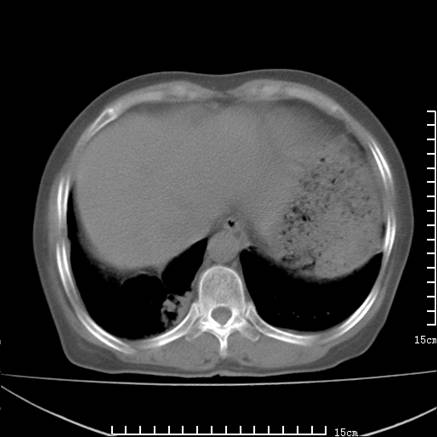

女,王某,58岁,咳嗽三个月余,基层医院二个月前诊为肺结核,用抗结核药二个月无明显疗效。

心包积液致肺瘀血.右侧周围型肺癌伴肺内转移,中间裂积液,叶间胸膜肥厚.右上肺大泡,右侧胸膜肥厚.

双肺继发型tb,心功能不全并肺淤血、心包、双侧叶间裂积液,肺大泡,右下胸膜肥厚钙化。